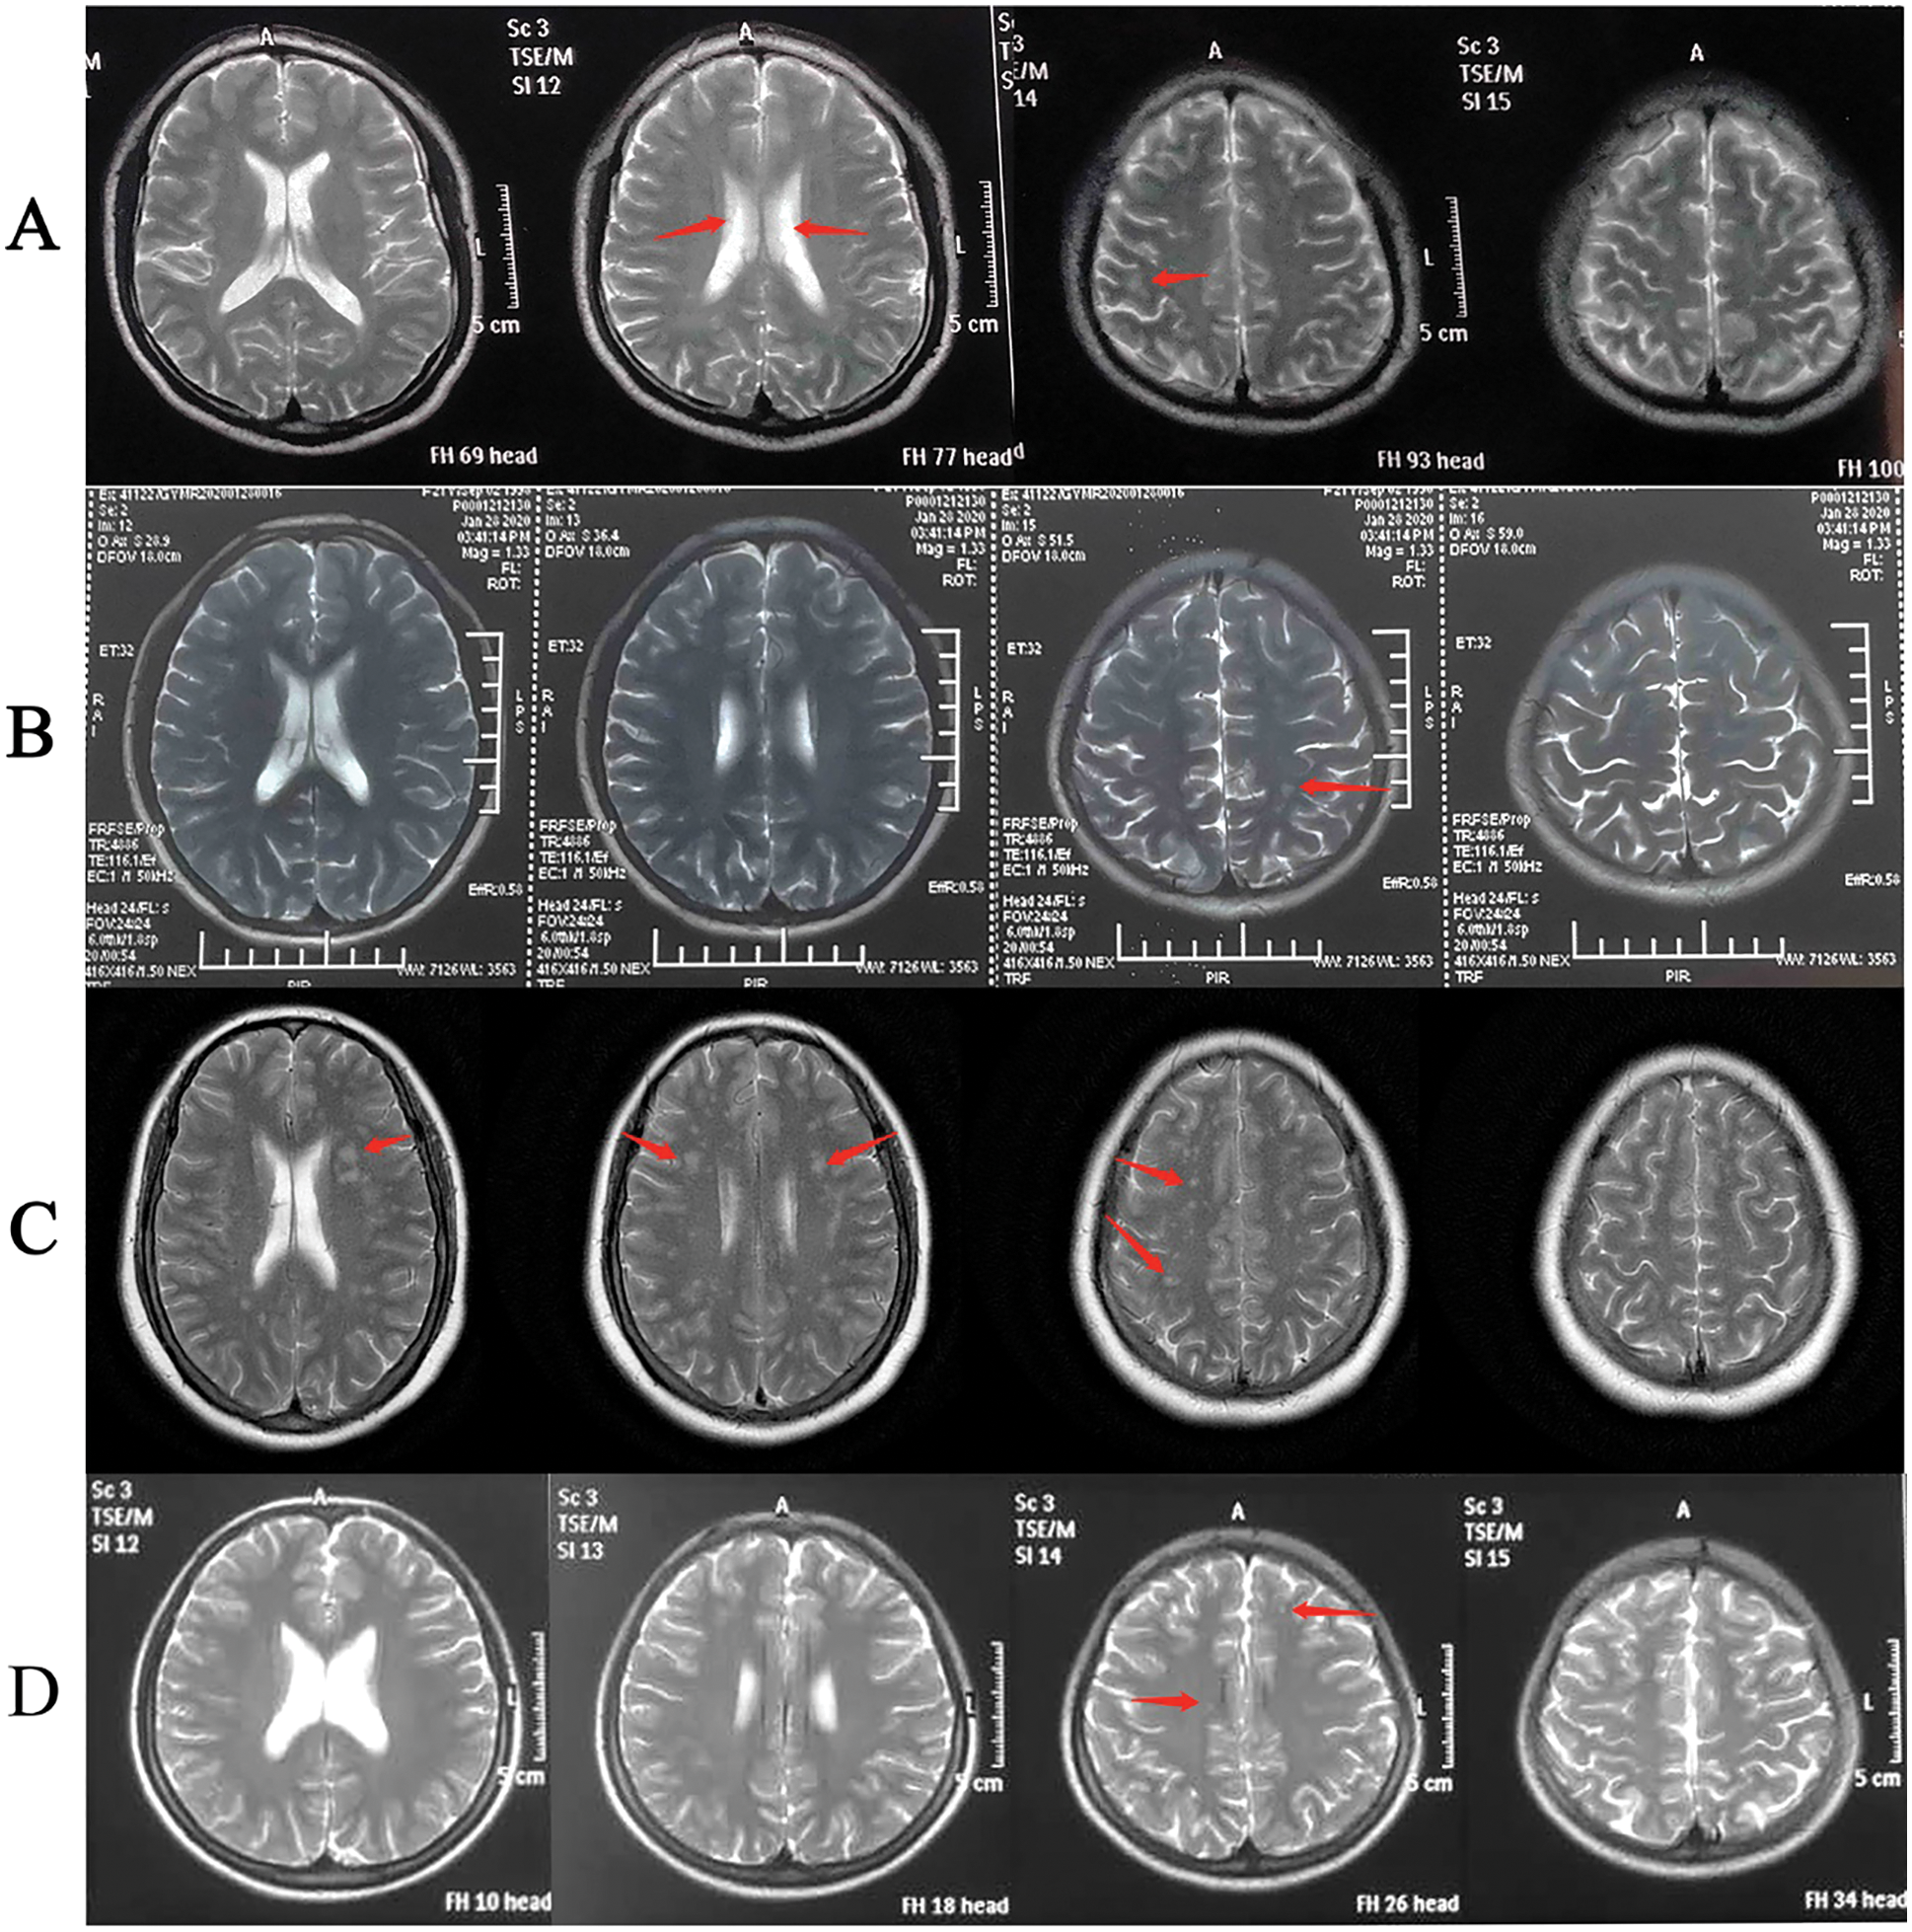

Five patients (ID: 2, 3, 5, 8, 11) carrying the pathogenic variants of NOTCH3 were suspected as CADASIL. To confirm the cerebral pathogenic phenotype, four patients (ID: 2, 5, 8, 11) undertook MRI. Patient 3 who had no neurologic symptoms refused to take the examination because of the short hospitalization time and the lack of MRI equipment in the local community. Although these patients denied suffering from Seizure, migraine and other neurological symptoms, Surprisingly, the cerebral MRI results of four cases showed that the presence of white matter changes, which conformed the CADASIL phenotype (Fig. 2). Patient 2 had a few white matter lesions in bilateral paraventricular and central posterior gyrus (Fig. 2A). Patient 5 had white matter scattered ischemic lesions in the cerebral hemisphere (Fazekas I) (Fig. 2B). Multiple lacunar lesions and mild white matter demyelination changes were presented in the bilateral basal ganglia and semi-oval central of Patient 8 (Fig. 2C). Patient 11 had a few white matter lesions in the left occipital lobe and the right radiating crown (DWML I) (Fig. 2D). The results of pulmonary vascular hemodynamic examination of five patients are shown in Table 3. All of five patients had severe pulmonary hypertension.

Figure 2: The cerebral MRI of Patients 2,5,8, and 11

To our knowledge, the etiology of PAH-CHD is complicated and affected by many factors, and the phenotype is heterogeneous [4]. Defining the cause is essential for the treatment of PAH-CHD patients [18]. CADASIL is the most prevalent inherited cause of cerebral small-vessel disease, cerebral autosomal-dominant arteriopathy with subcortical infarcts and leukoencephalopathy, a disorder linked to mutations in NOTCH3 [19,20]. The pathophysiology of CADASIL mainly includes cerebral infarction, cerebral hemorrhage, and white matte changes, etc. [19,21]. In our study, four out of five patients carried the same NOTCH3 mutation (c.1630C>T, p.Arg544Cys). One patient carried NOTCH3 c.224G>A, which has been reported in patients with a CADASIL phenotype [20]. Moreover, NOTCH3 c.224G>C mutation in the same position has been indicated to be pathogenic in several studies [22–25]. According to American College of Medical Genetics and Genomics (ACMG) guideline [26], NOTCH3 c.224G>A was a likely pathogenic mutation. Patients 2, 5, 8 and 10 displayed CADASIL image characteristics of cerebral MRI (Fig. 2), which conformed to the CADASIL phenotype.